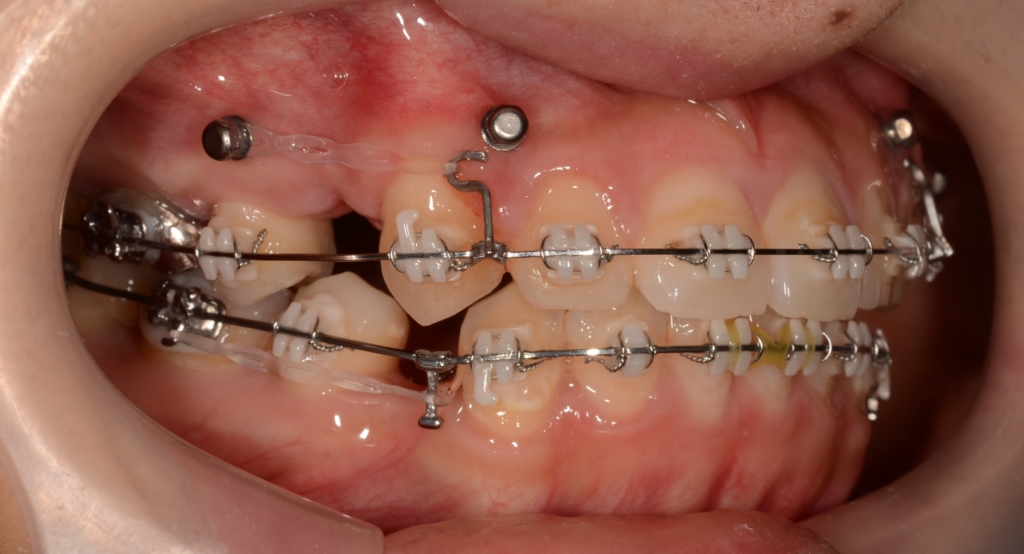

【前歯を引っ込める】

次は第二希望である「口ゴボの改善」のために、抜歯を行い、上下とも前歯を最大限に引っ込めるように治療を進めます。

圧下の時に使ったアンカースクリューがそのまま利用できたことは幸いでした。

合わせて仕上げの調整を入れたり・・・ちょこちょこと修正を挟みながら、治療はエンドロールへ向けて進みます。